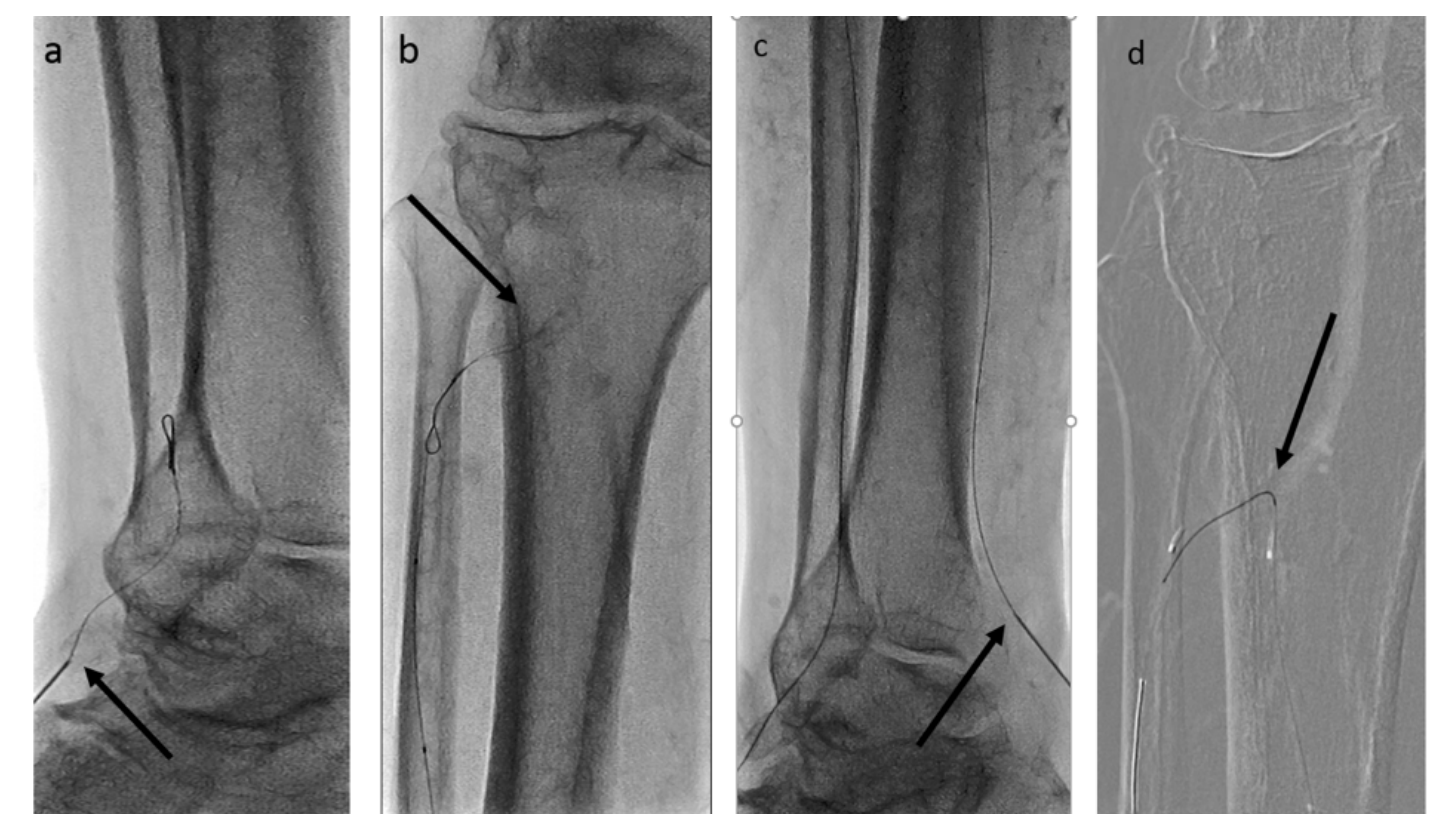

Anticipating a high risk of complications related to transfemoral access, we decided to proceed with a TAMI approach utilizing transradial guidance. A 4 to 5 French (Fr) Glidesheath Slender sheath (Terumo) was inserted in the right radial artery for visualization of the proximal vessels. We placed a 2.9 Fr Cook pedal sheath (Cook Medical) in the AT and advanced an .018-inch CXI support catheter (Cook Medical) over an .018-inch Command ST wire (Abbott Vascular). The CXI catheter and wire were advanced through the course of the ATA intraluminally, except for the ostium of the ATA, where the wire entered a subintimal space. Thereafter, we gained access in the right PT with a 4 to 5 Fr Glidesheath Slender sheath to serve as an antegrade access to cross the ATA CTO (Figure 2). An .018-inch CXI support catheter was telescoped within a 4 Fr Berenstein catheter (Boston Scientific) with an .018-inch Command wire advanced into the proximal AT (Figure 3). The antegrade equipment was advanced into the distal AT. The retrograde CXI catheter was pulled back in the distal AT, where the antegrade wire was inserted for externalization. Subsequently, the antegrade CXI catheter was externalized through the retrograde 2.9 Fr sheath placed in the distal AT (Figure 4). The .018-inch Command wire was exchanged for an .014-inch ViperWire (Cardiovascular Systems, Inc. [CSI]) guidewire to perform atherectomy using a 1.5 mm classic crown Diamondback 360 catheter (CSI) in the PT, TPT, and AT (Figure 5). Thereafter, based on extravascular ultrasound (EVUS) measurements, we performed balloon angioplasty of the proximal DP, AT, and PT with a 3.5 x 300 mm Ultraverse balloon (BD), and TPT with a 4.0- x 60-mm Lutonix drug-coated balloon (BD) with an excellent result (Figure 6).